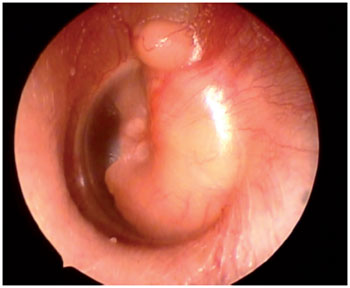

The patient consulted our institution when her symptoms persisted. She had no complaints of hearing loss or otorrhea. On examination, the patient was found to be in good general condition and without neurological deficits. Otoscopy of the right ear was normal, but a retrotympanic, non-pulsatile mass was detected in the left ear (Figure 2). Figure 3 demonstrates her puretone audiometry, with a 10dB-gap in the left ear. She subsequently underwent a left radical mastoidectomy with total resection of the lesion. Intraoperatively, the tumor had a fibrous aspect and filled the antrum and the entire tympanic cavity, involving the ossicular chain. The histopathological study was compatible with middle ear adenoma with neuroendocrine differentiation.

Figure 2. Otoscopy of the left ear demonstrating a retrotympanic non-pulsatile mass.